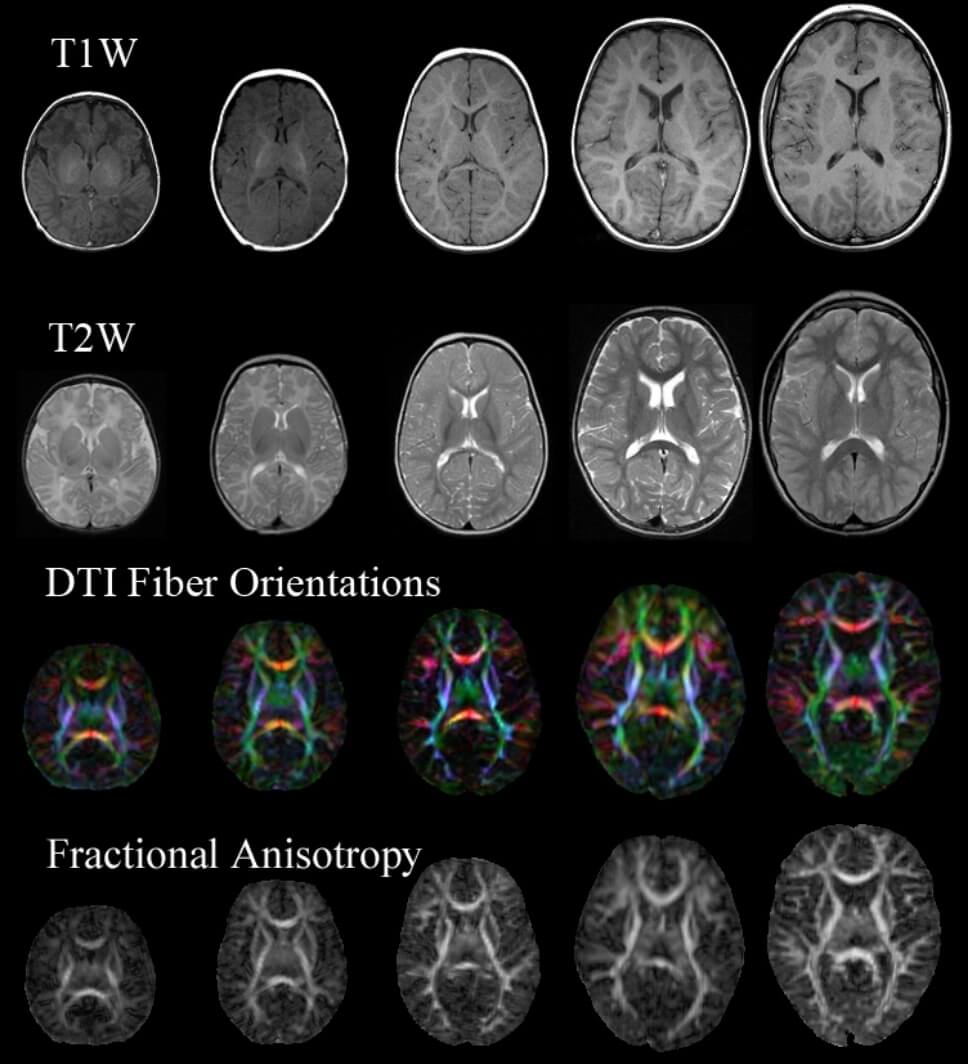

IRM cérébrale

Nous examinerons votre cerveau à l’aide d’un appareil d’imagerie par résonance magnétique (IRM) de 7 teslas.

L’imagerie par résonance magnétique est une technologie non invasive très sensible à la teneur en eau et en fer des cellules du corps. Cet appareil à champ élevé peut détecter les signaux des cellules cérébrales avec une grande précision et produire des images à haute résolution de l’anatomie du cerveau, ou des cartes de son organisation fonctionnelle ou métabolique. (À quoi s’attendre?)